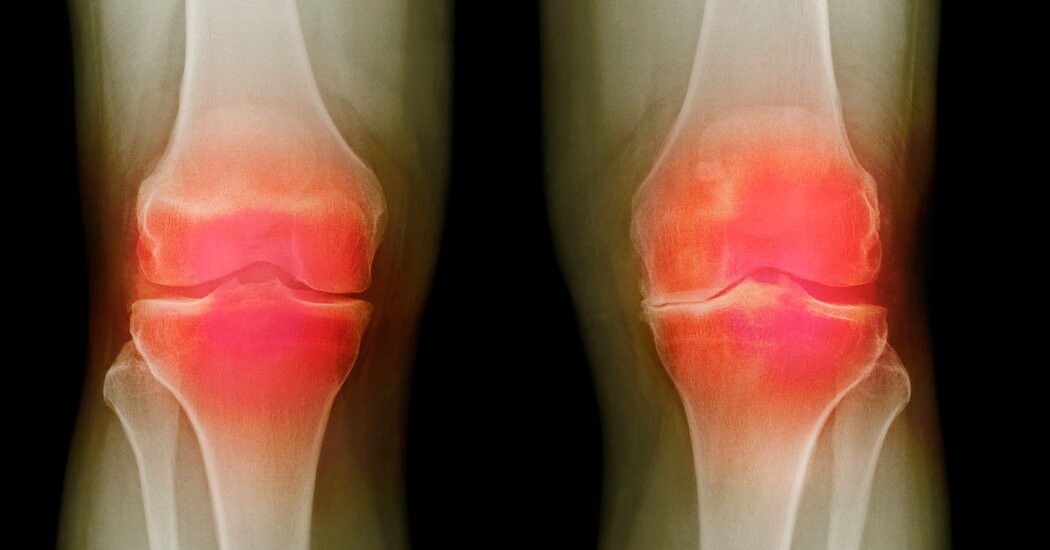

Остеоартрит характеризується прогресуючим руйнуванням тканин суглоба, що призводить до хронічних болів, втрати рухливості і, часто, необхідності проведення інвазивних операцій із заміни суглоба. Протягом десятиліть лікування здебільшого фокусувалося на купуванні симптомів — таких як знеболювання та фізіотерапія, — а не на усуненні першопричини ушкоджень.